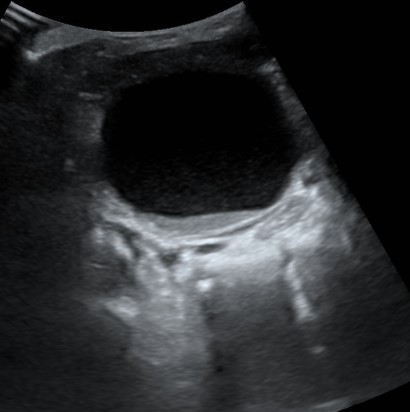

A su llegada a Urgencias, se realiza radiografía de abdomen sin alteraciones y ecografía abdominal en la que se objetiva dilatación uretero-pielo-calicial bilateral (Fig. 1) además de distensión vesical con nivel líquido-sedimento y discreto engrosamiento de pared (Fig. 2).

Figura 2. Distensión vesical con nivel líquido-sedimento y discreto engrosamiento de pared